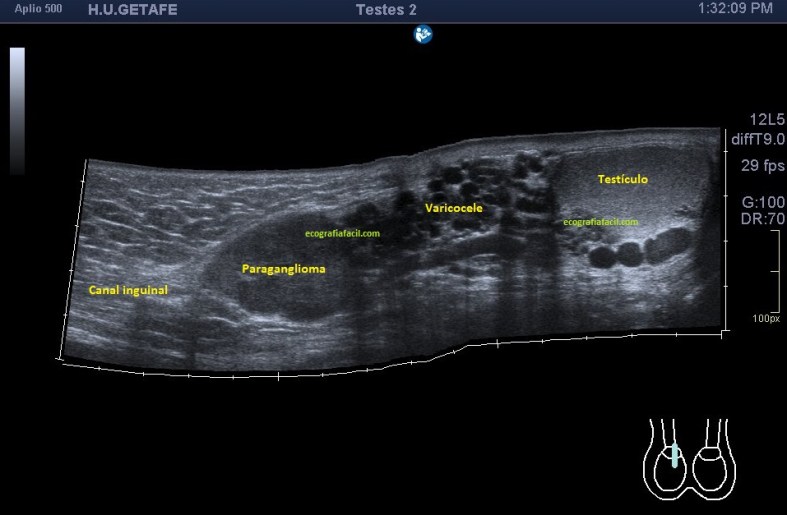

En cuanto la paciente me indicó su zona de dolor y pude el transductor observé una imagen mal definida que ocupaba la porción inferior del músculo recto abdominal derecho (coincidiendo con foco doloroso), se visualiza una lesión de ecogenicidad heterogénea (predominio hipoecogénico) con bordes irregulares de aproximadamente 2,5 cms en su eje más largo.

En este estudio, el estudio (perdón por la redundancia) contralateral no afectado es muy importante, diría yo, que una vez hecho el primer contacto con la lesión, lo primero es ir a comprobar la semiología del músculo y su ecoarquitectura normal. Encontramos en la zona contralateral sana un músculo de aspecto en “cielo estrellado”(punteado sobre fondo hiperecogénico) en el corte transverso y en forma de “penacho”(fibras alargadas hiperecogénicas sobre el fondo hipoecogénico de músculo) en longitudinal.

Semiológicamente es evidente una desestructura en el vientre muscular de recto anterior, que borra el aspecto normal del músculo y lo aumenta de tamaño aumentado su hipoecogenicidad. Los bordes son irregulares y de márgenes mal definidos.

La imagen final demuestra una visión panorámica de los rectos abdominales inferiores demostrando los hallazgos que te he ido explicando durante el post. En este caso me hizo falta utilizar una función del ecógrafo muy útil que es la “función dual”, donde he dividido a pantalla en dos y he podido comparar en una misma imagen tanto a normalidad como la zona patológica, con un considerable aumento de la resolución de la imagen y un aumento en la calidad global de esta tanto en corte transverso como en longitudinal. Esta función dual permite el estudio comparativo con doppler. Muy útil, aunque el almacenamiento masivo de imagen en el pacs hace que esta función haya caído paulatinamente en desuso.

Estos hallazgos dado el contexto clínico sugieren foco de endometriosis. En este caso eran focos o implantes de endometriosis que tras la cirugía pudieron quedar diseminados por el tejido muscular.